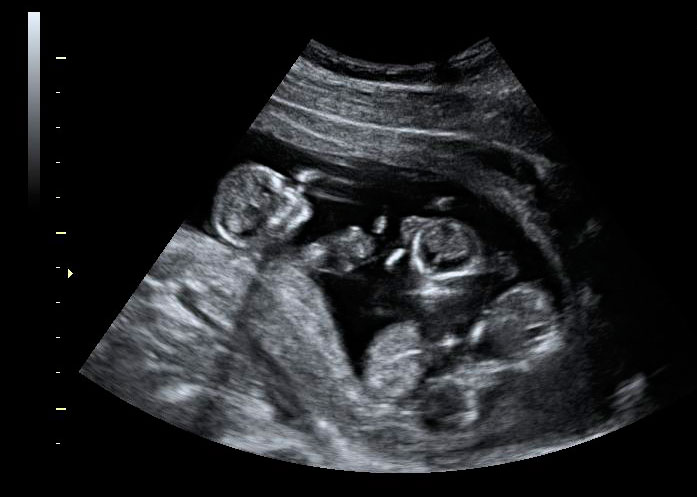

Ecografía Embarazo 2D y 3D Semana 12 - CRIBADO DEL PRIMER TRIMESTRE